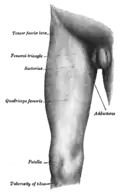

Front and medial aspect of right thigh.